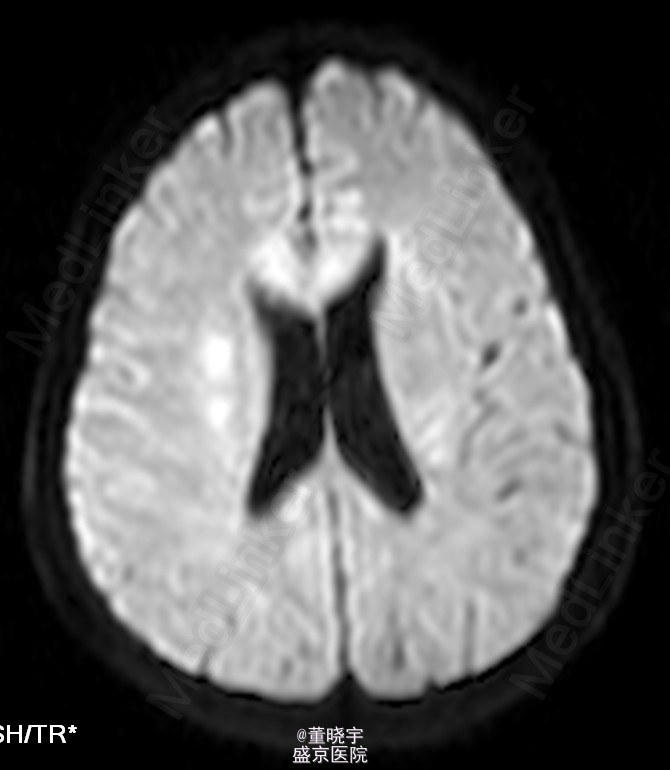

神经系统专科查体:神清语明,双瞳等大正圆,D=4.0mm,对光反射迟钝,视力丧失,双眼球各向运动充分,无复视及眼震,额纹对称,双侧鼻唇沟对称,伸舌居中,转颈有力,四肢肌力Ⅴ级,肌张力正常,双上肢指鼻准确,双下肢跟膝胫试验稳准,BCR L++R++, TCRL++R++,PSRL++R++,Babinski征L+R+,Hoffmann征L-R-,颈强,双掌颏反射(+)。 辅助检查:腰穿压力200mmH2O,细胞总数28*10^6/L,白细胞24*10^6/L,氯化物118.0mmol/L,糖2.41mmol/L,蛋白2.1g/L。 视觉诱发电位:双侧视通路传导障碍。 颅脑MRI见上。 核抗体(ANA)阳性;抗SS-A及抗SS-B抗体均阳性;IgG、IgA升高;补体 C3、C4下降。

诊断:原发性干燥综合征合并中枢损害 处理:静脉点滴丙种球蛋白治疗,临床症状稳定后出院口服强的松片10毫克/天。

半年后患者再次入院复诊,复查颅脑MRI提示新增病灶,但风免相关化验未见改变,急性长期口服激素治疗。 讨论:原发性干燥综合症(pSS)是一种以唾液腺和泪腺腺体淋巴细胞浸润和破坏为特点的自身免疫性疾病,临床主要表现为眼干、口干。腺体外表现主要是由于类似的单核细胞浸润或血管炎引起。CNS-SS的发病率及其颅脑MRI表现目前仍存在争议,有文献报道CNS病变发生率为0%-60%[1]。既往的一个400例患者大样本研究发现,只有1%患者合并CNS并发症。 CNS-SS的临床表现多样,脑部病变包括局灶性和弥漫性病变,局灶性病变主要表现为局部感觉和运动异常、失语、癫痈发作、构音障碍和视觉减退等;弥漫性病变主要表现为亚急性或急性脑病、无菌性脑膜脑炎、心理障碍和认知障碍等。中枢神经系统病变多隐匿起病,少部分患者呈急性或亚急性起病,部分患者同时合并有周围神经系统损害,加上部分pSS患者以中枢神经系统损害为首发症状,使得临床症状表现多样,诊断困难,极易误诊、漏诊并延误治疗。 目前对于pSS合并中枢神经系统病变治疗还没有统一的方案,大剂量激素治疗是目前临床中常用的方法之一,也有报道对于激素效果不佳的患者合并应用环磷酰胺也收到了不错的效果。静脉注射丙种球蛋白(IVIg)也是免疫相关的中枢神经系统病变常用治疗手段之一,尽管外文报道IVIg对于pSS引起的周围神经病变效果明显。